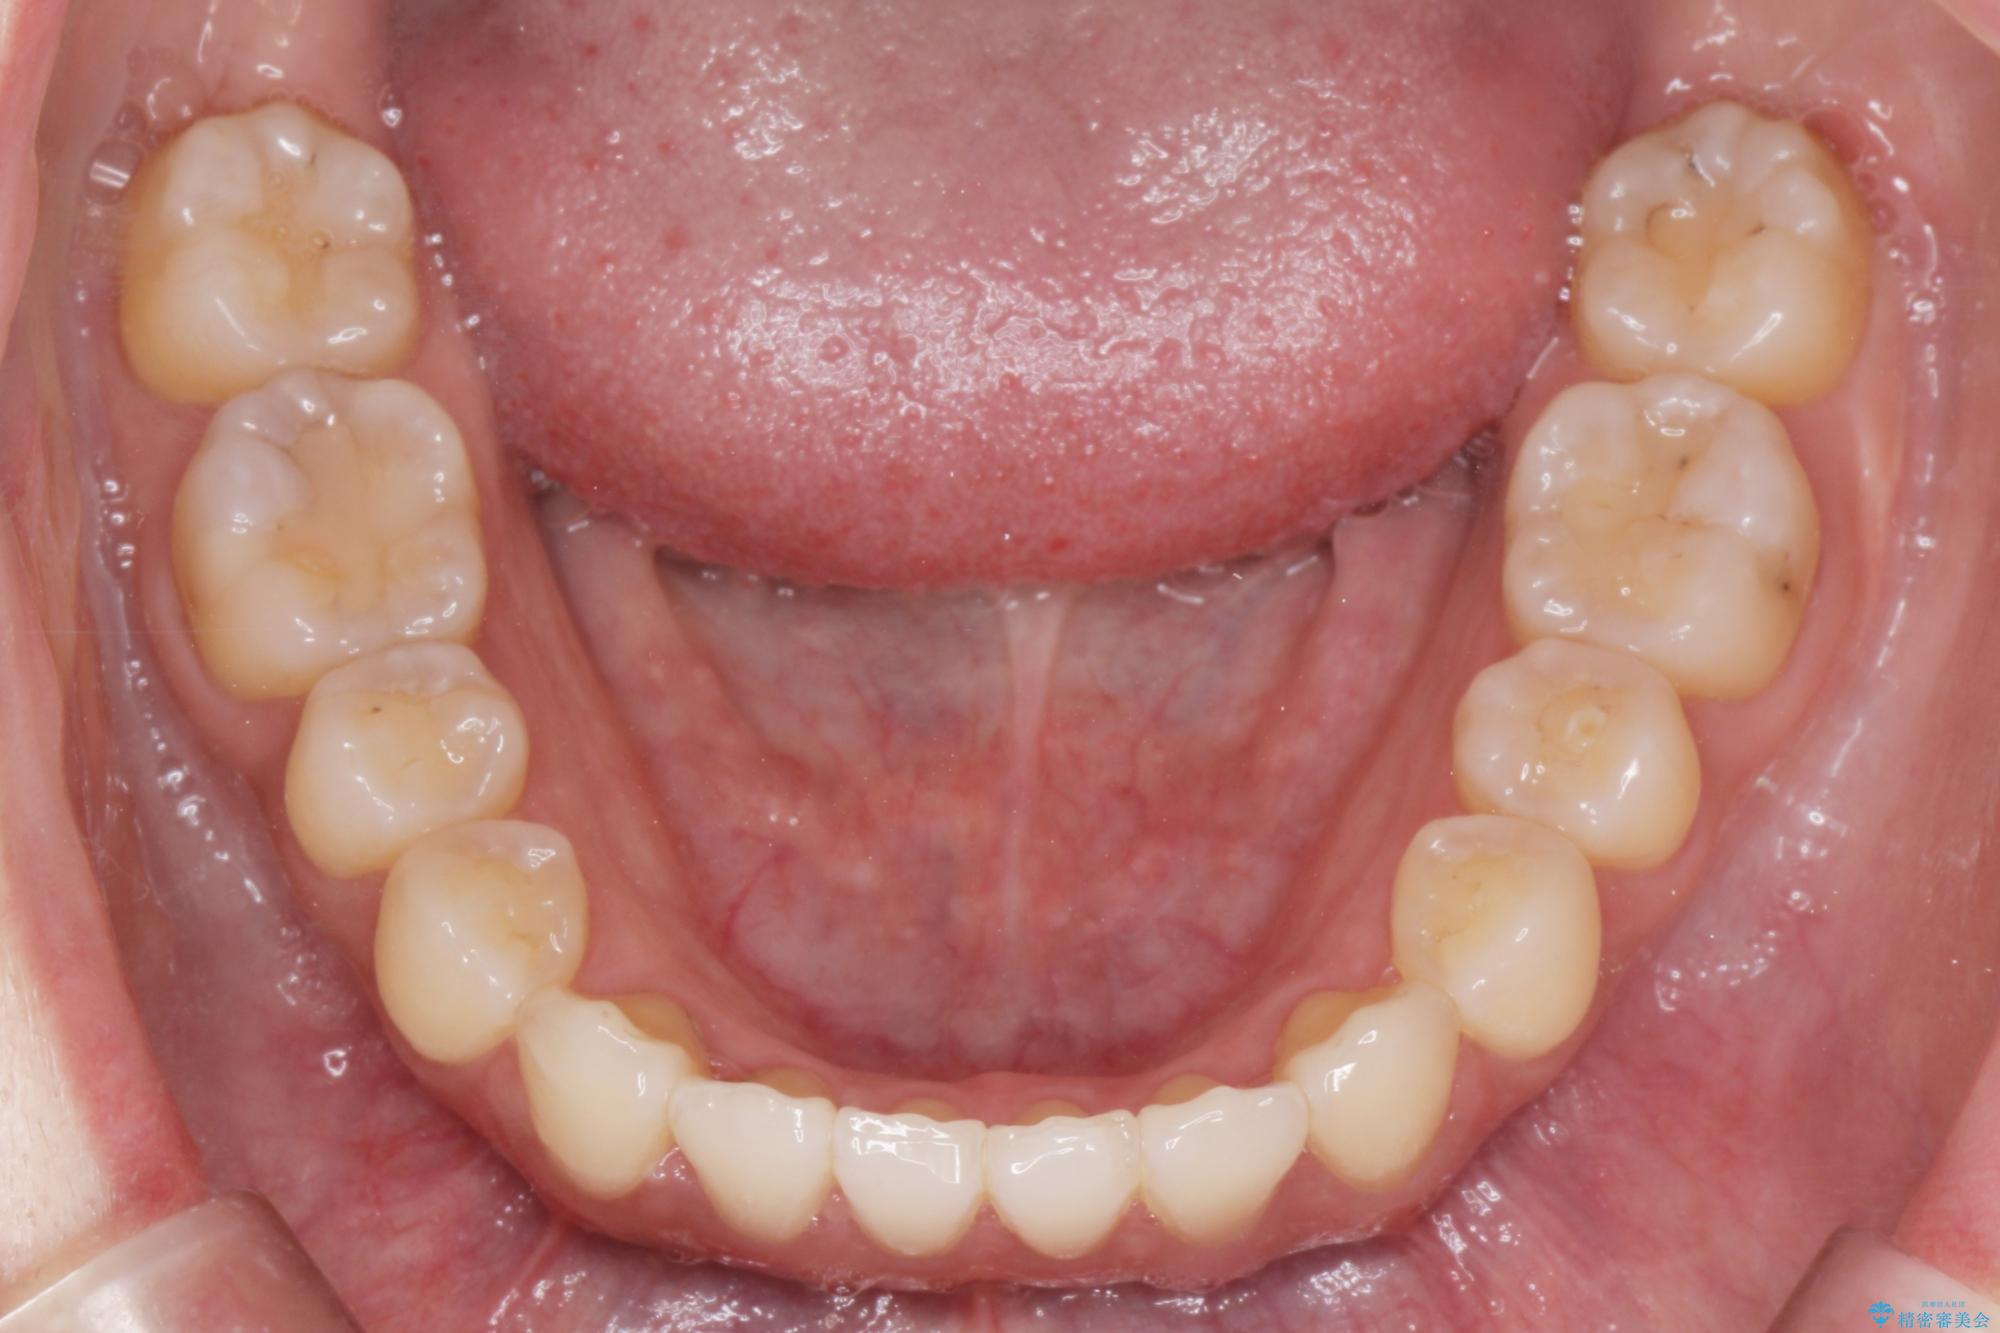

前歯のねじれが気になる、歯並びを改善したいとご来院された患者様です。

歯のねじれをきれいに取るのは、インビザライン(マウスピース矯正)だけでは難しい動きです。そのため、事前に4か月間の部分ワイヤー矯正を行い、治療期間を短くし、より美しい仕上がりを目指す計画です。

前歯が綺麗に並び、大変ご満足いただけました。